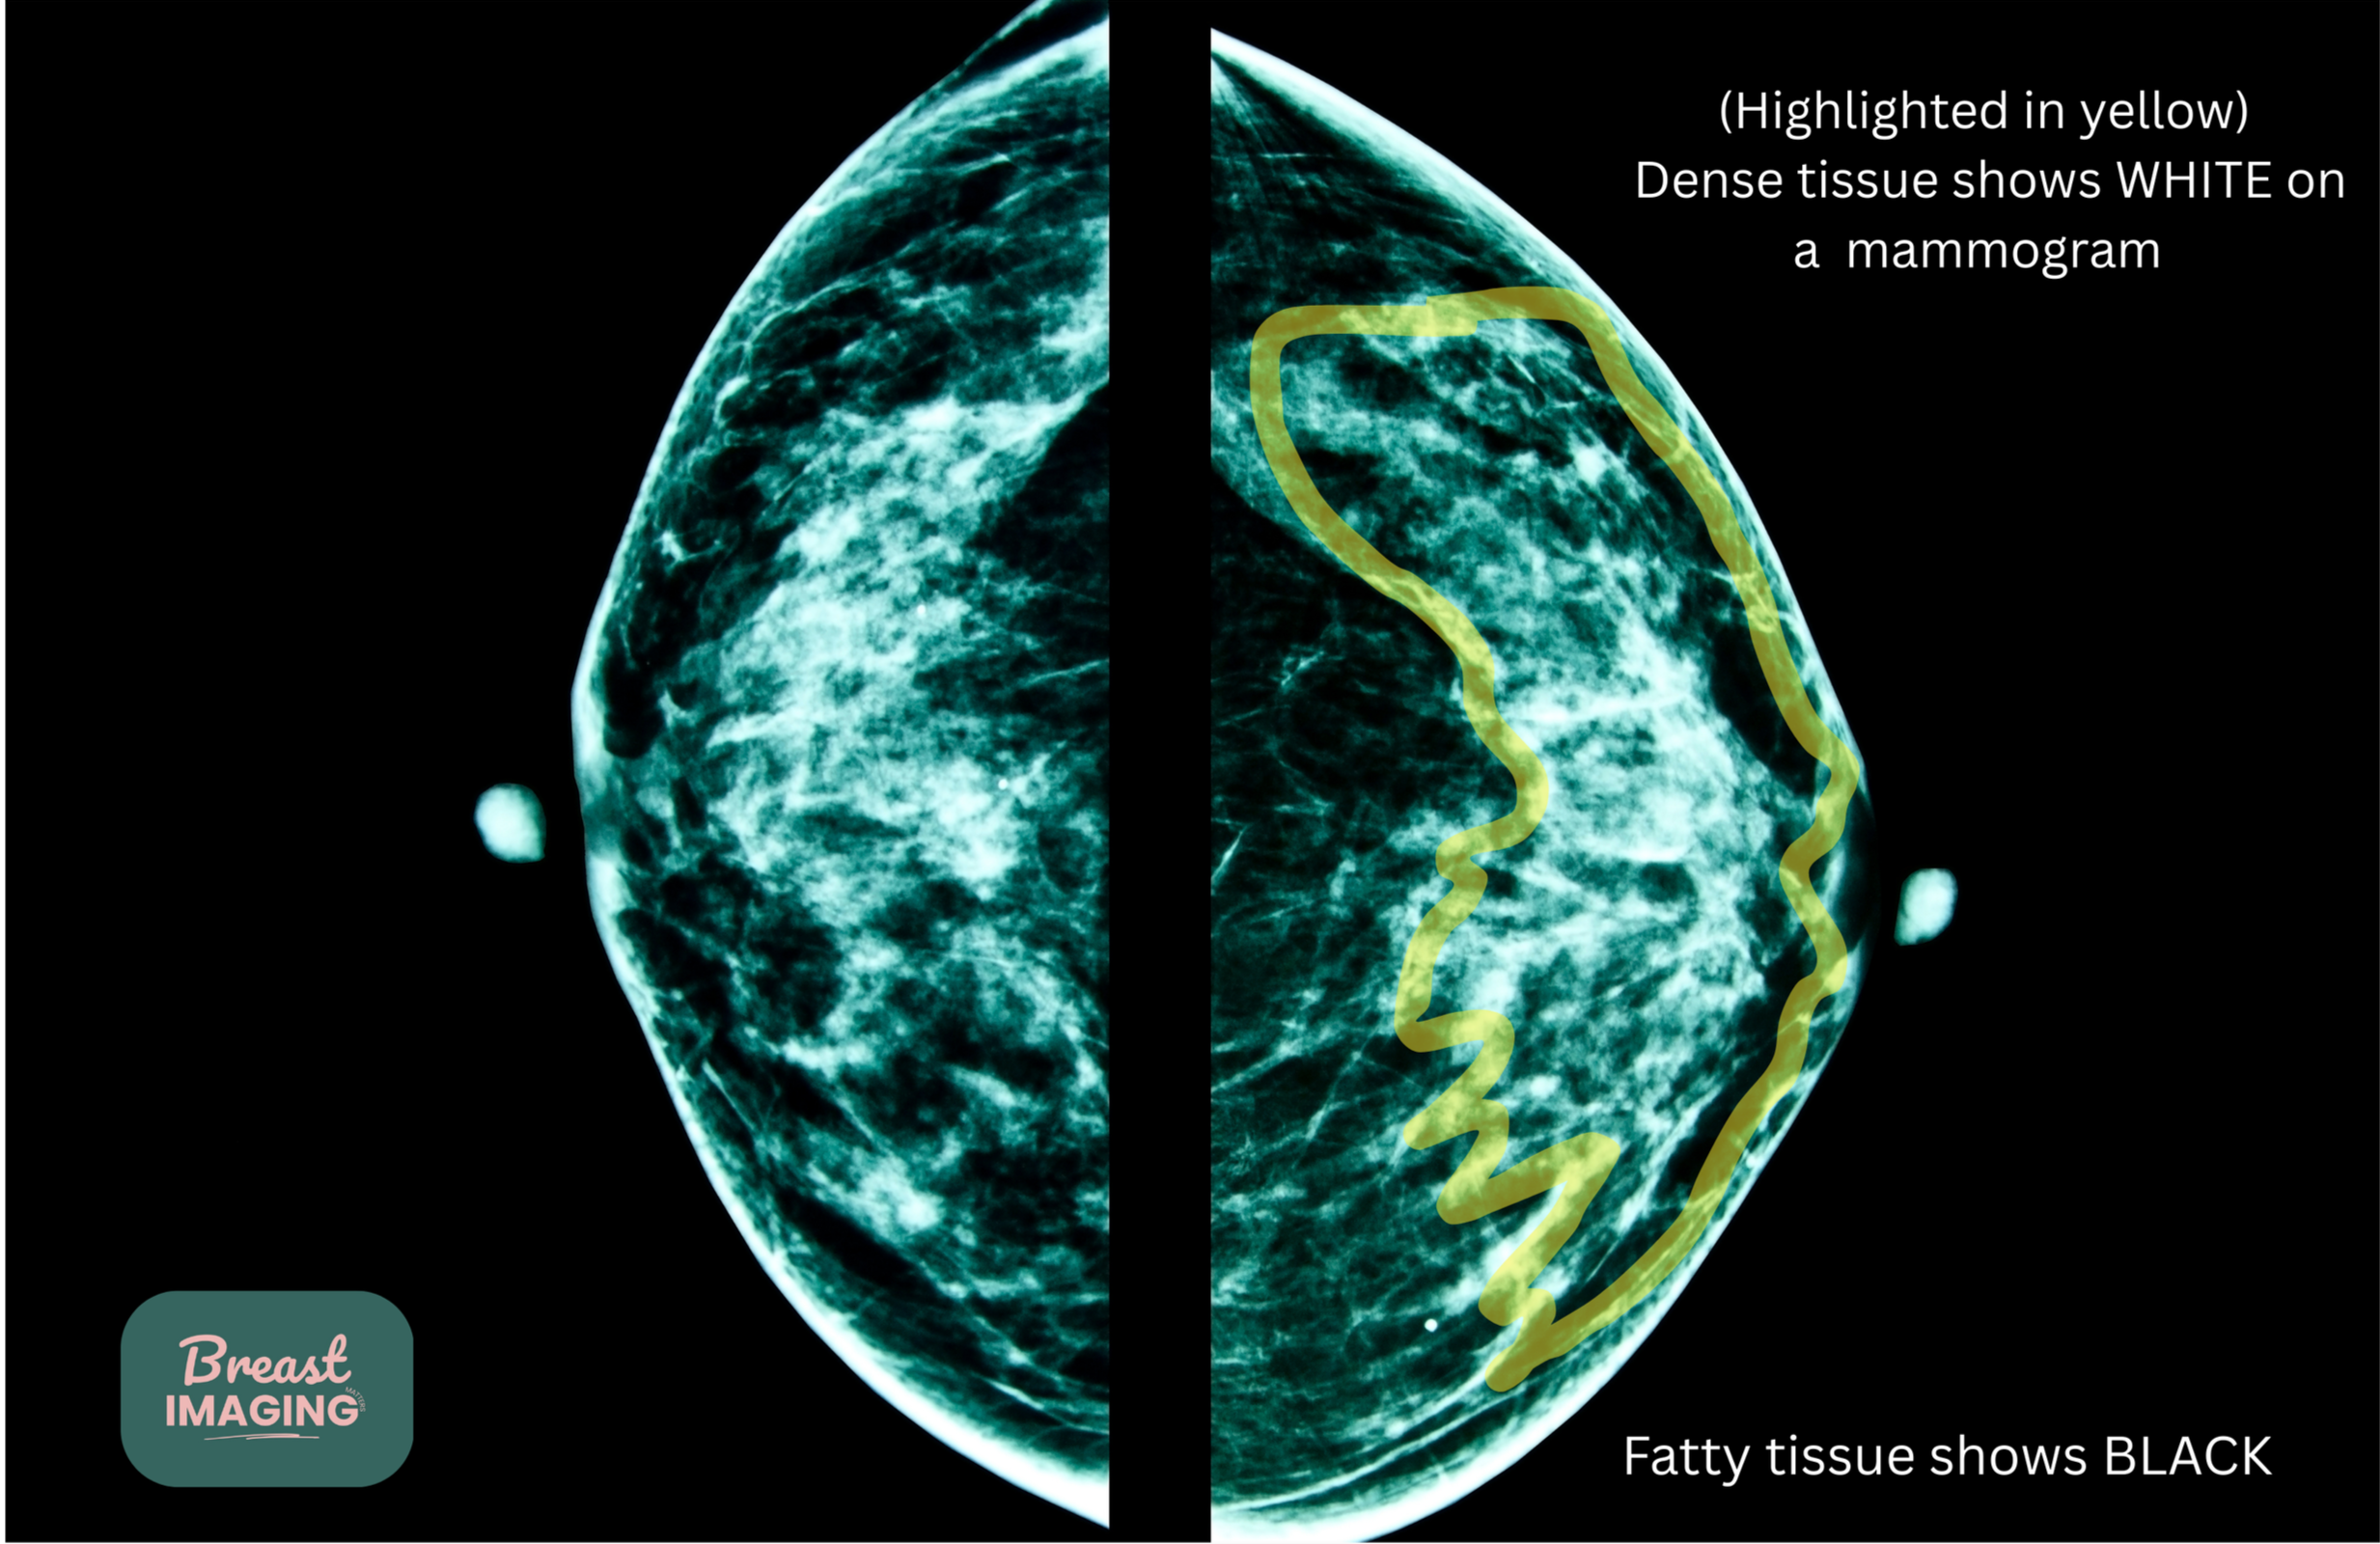

Breast density refers to the amount of fibroglandular tissue compared to fatty tissue seen on a mammogram. It is a normal and common finding.

Breast density cannot be determined by how breasts feel on exam — it is assessed by the radiologist when your mammogram is interpreted.

Breasts are typically categorized into four density groups ranging from mostly fatty to extremely dense.

Dense breast tissue is common, but it can make some findings more difficult to visualize on mammography because both dense tissue and many abnormalities appear white on imaging.